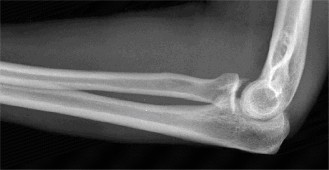

The patient undergoes resection arthroplasty with antibiotic cement spacer and a 6-week course of IV antibiotics. He returns to clinic 4 months later with improved pain, CRP <3, however, on examination he has a positive belly press sign and increased external rotation compared with the contralateral shoulder. Imaging is shown in Figure 2–57.

Figure 2–57

The correct answer is (D). The patient has completed his course of antibiotics and his spacer and is now an appropriate candidate for explanation of the cement spacer with revision shoulder arthroplasty, therefore Choices A and C are incorrect. The patient’s clinical examination findings point to rotator cuff tear (specifically subscapularis) which has occurred in the interval between his obtaining his initial total shoulder arthroplasty and his current examination. Therefore, total shoulder arthroplasty (Choice B) is contraindicated, and the patient should have a reverse total shoulder arthroplasty. Objectives: Did you learn...? Recognize the clinical presentation of a patient with infection after total shoulder arthroplasty?